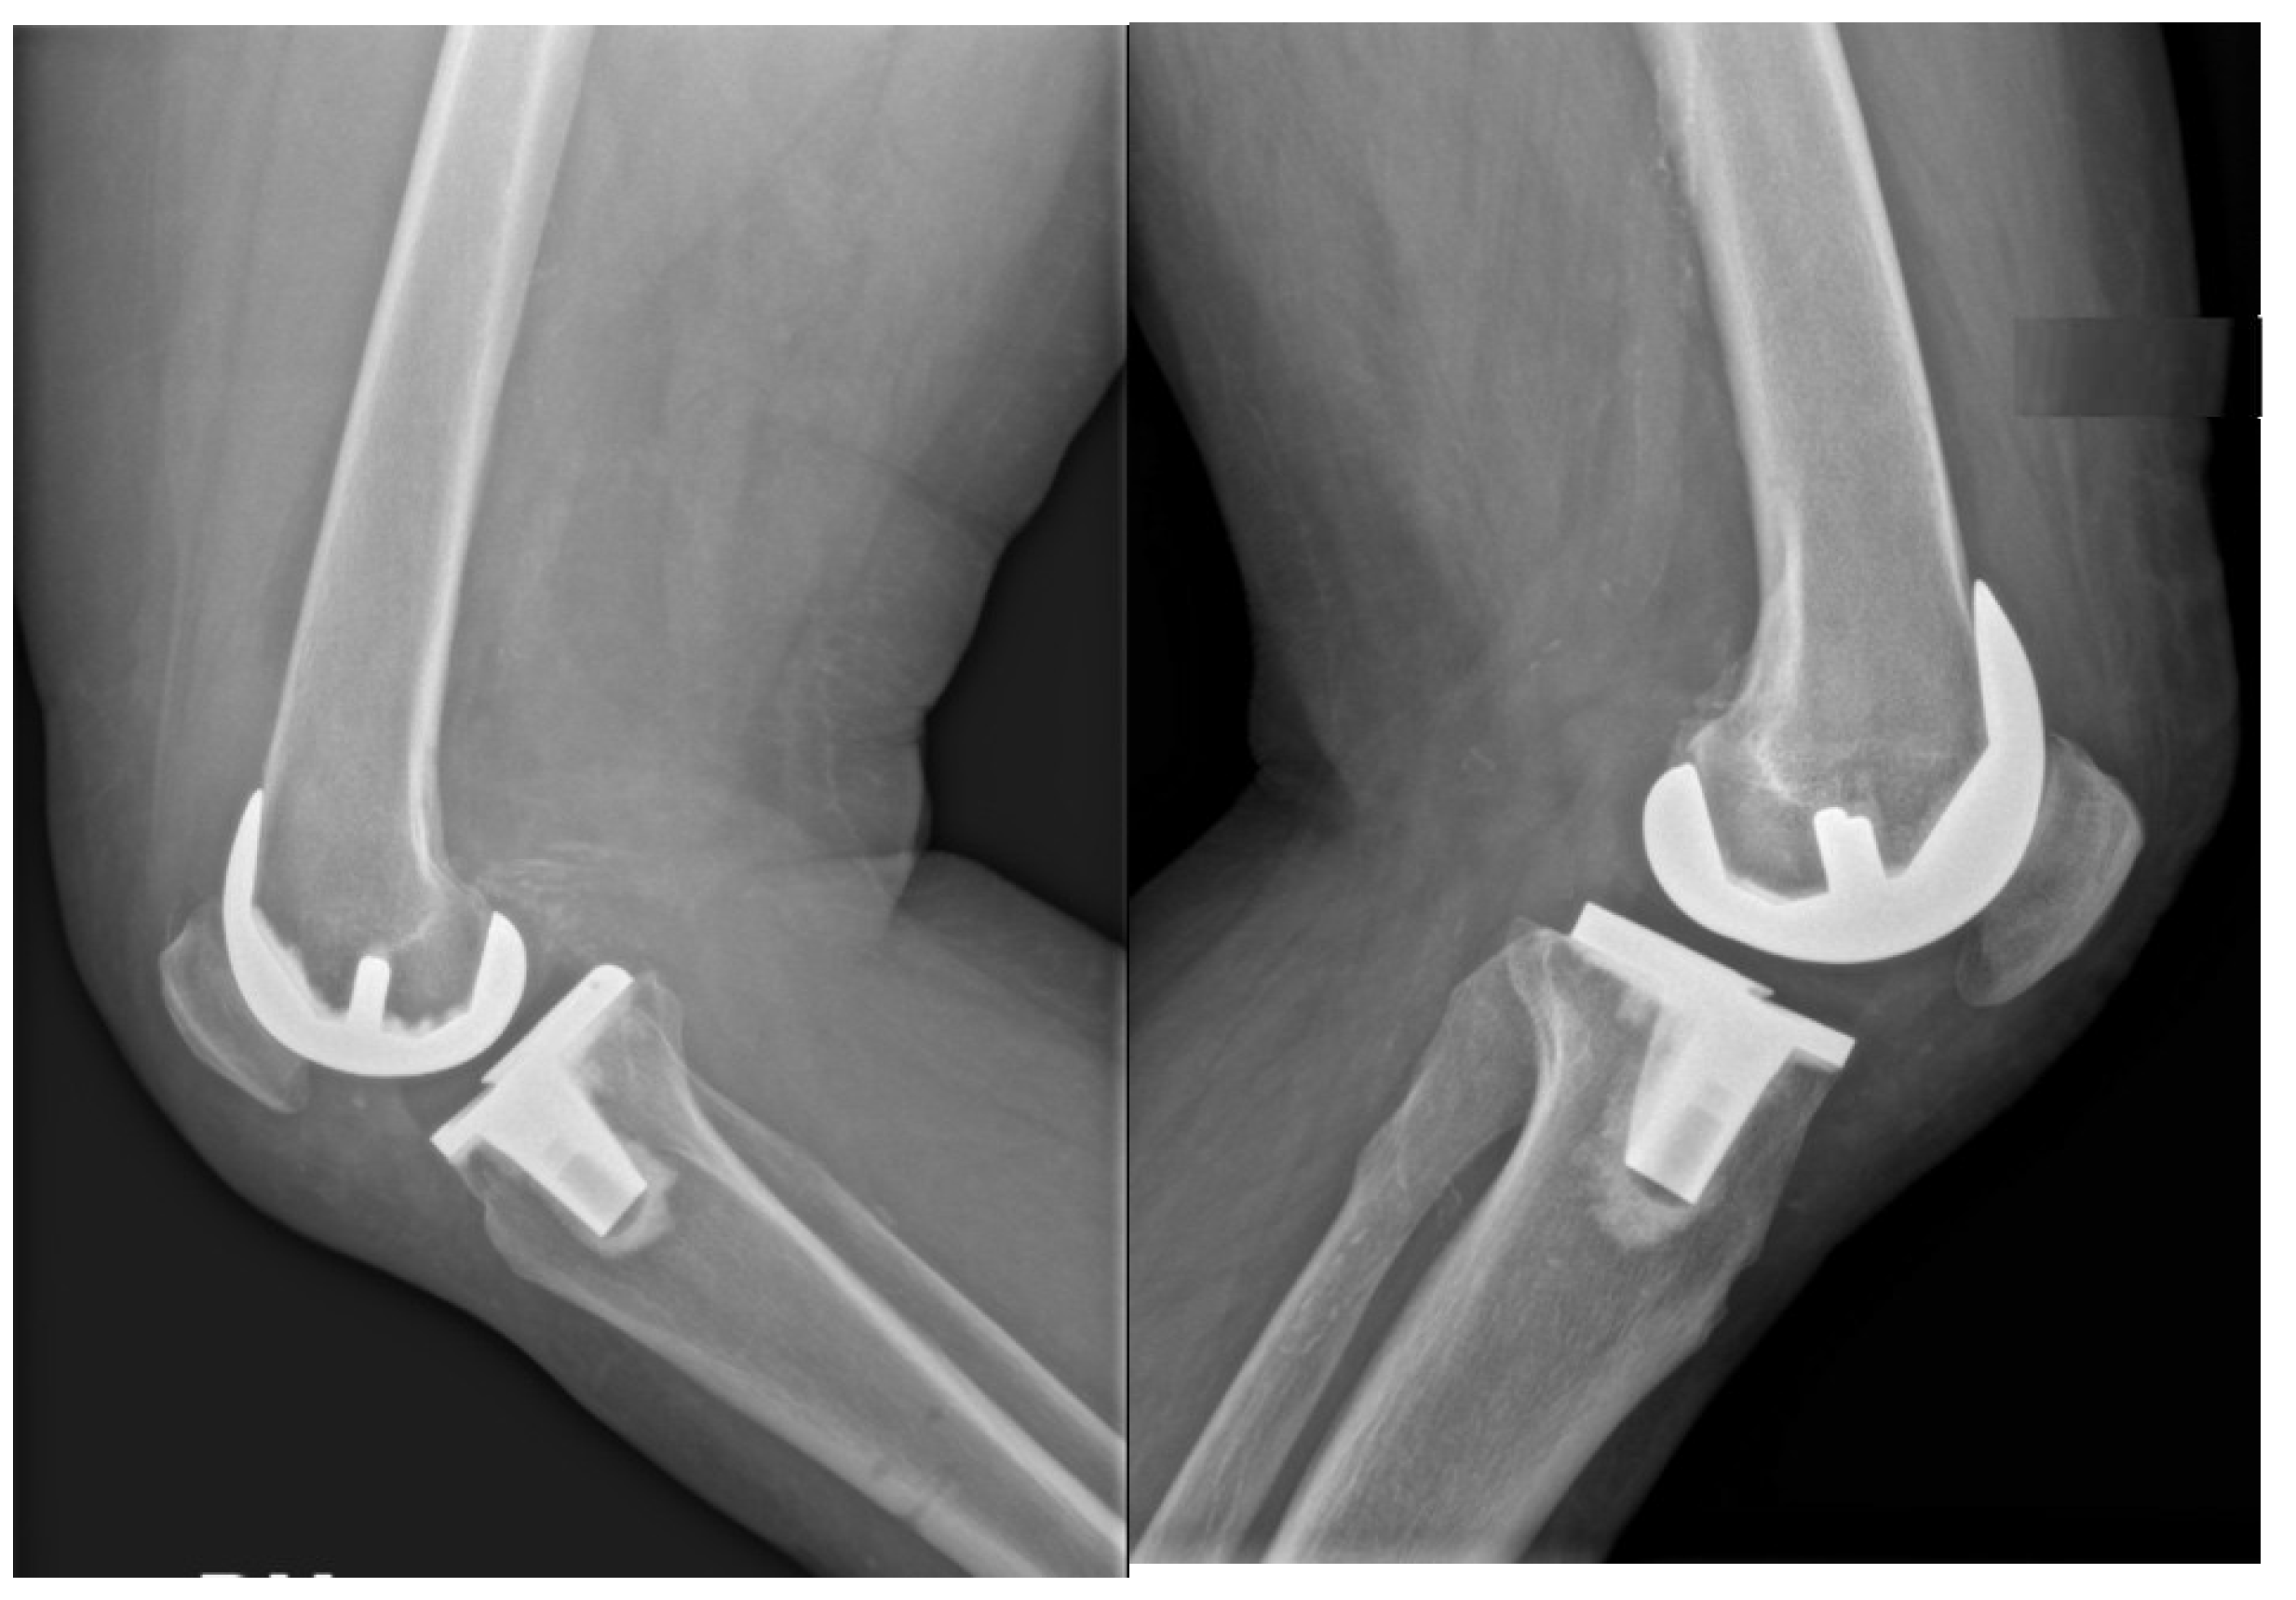

According to limitations previously highlighted [19], the planned intraoperative MPTA, LDFA, HKA, DFF, and TS angles of bone resections were extracted from the surgical report generated by the ROSA Knee System. Postoperative evaluation of radiographic outcomes was conducted three months postoperatively, and angle measurements were performed, as shown in Table 1. Standardized full-length weight-bearing anteroposterior lower limb radiographs and lateral 90° flexion knee and axial radiographs of the patella were obtained (Figure 1, Figure 2 and Figure 3). Incomplete radiographs because of a lack of weight bearing or incomplete extension warranted the exclusion from the present study. The arithmetic mean was calculated for each measurement performed by the two observers, and the obtained values were used for statistical purposes. Outliers from target angles were considered as follows: MPTA 90° ± 3°, LFDA 90° ± 3°, HKA 180° ± 3°, DFF 3° ± 3°, and TS 7° ± 3.

No significant differences were found between planned (robotic) and achieved (radiographic) results for femoral and tibial coronal angles and HKA (Table 4 and Figure 1).

Figure 2. Example of a lateral 90° flexion knee radiograph used for measurements.